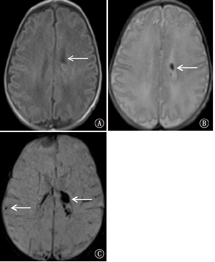

局限性缺血性脑损伤MRI表现为半卵圆中心、侧脑室周围斑片状T1WI高信号、T2WI低信号,DWI序列呈明显高信号。弥散性缺血性脑损伤在DWI上表现侧脑室周围大片状高信号。脑室周围白质软化MRI表现为侧脑室周围斑片状T1WI低信号、T2WI高信号,DWI序列呈低信号(图1)。

注:A:左侧侧脑室周围斑片状T1WI低信号;B:左侧侧脑室周围斑片状T2WI高信号;C:弥散加权成像上左侧侧脑室周围低信号,弥散未受限灶 A: T1-weighted magnetic resonance image showed patchy decreased signal intensity in the left periventricula; B:T2-weighted magnetic resonance image showed increased signal intensity in the left periventricula; C:diffusion weighted imaging showed decreased signal intensity focus that diffusion was not restricted in the left periventricula